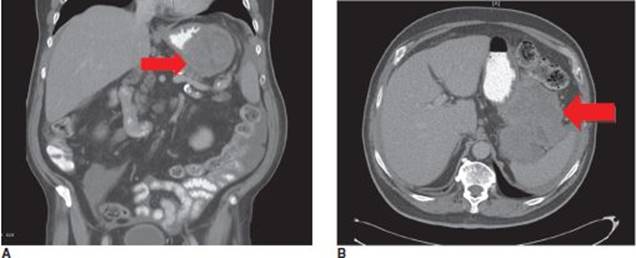

A 68-year-old, otherwise healthy man presents with early satiety and vague upper abdominal pain, which became progressively worse over the past several months. His symptoms are unrelieved by proton pump inhibitors and have worsened in the past 2 weeks prompting him to see his primary physician. His past medical history is significant for hypertension and hyperlipidemia controlled with medications. His surgical history is unremarkable. Review of systems is negative for any other symptoms. Vital signs are normal. Physical examination reveals an upper abdominal mass, no associated jaundice, and no generalized lymphadenopathy. Contrast-enhanced CT scan of the abdomen and pelvis demonstrates a large, heterogeneous, partially necrotic left upper-quadrant mass inseparable from the gastric fundus (Figure 1). There is no radiographic evidence of metastatic disease.

FIGURE 1 • CT scan demonstrating a large, heterogeneous, partially necrotic left upper-quadrant mass inseparable from the gastric fundus. Also note reactive perisplenic fluid.